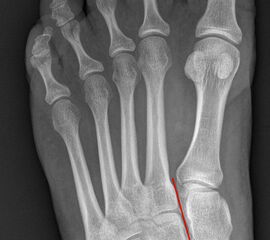

Auf den dp-Aufnahmen sollte der mediale Rand der Metatarsale-2-Basis mit dem medialen Rand des Os cuneiforme intermedium eine homogene Linie ohne Stufenbildung bilden (Abb. 7+8). Außerdem ist auf den Abstand zwischen der Metatarsale-1- und -2-Basis zu achten. Dieser sollte nicht größer als 2 mm bzw. im Vergleich zur Gegenseite nicht mehr als 1 mm erweitert sein. In bis zu 90% der Fälle zeigt sich ein sogenanntes „Fleck sign“ (Abb. 9), ein knöchernes Fragment zwischen der Metararsale-1- und -2-Basis im Sinne eines knöchernen Ausrisses des Lisfranc-Ligaments an der Metatarsale-2-Basis 211936410. Oft liegen zusätzliche Frakturen der Metatarsalebasen oder der Tarsale vor, die ebenfalls identifiziert werden sollten. Bei jeder Mittelfußbasisfraktur sollte umgekehrt an eine Lisfranc-Verletzung gedacht werden.

In der Schrägaufnahme sollte der mediale Rand des Cuboids mit dem medialen Rand der Metatarsale-4-Basis eine homogene Linie bilden.

Zum Lesen der Bildbeschreibung und zur Vollansicht bitte die Bilder anklicken.